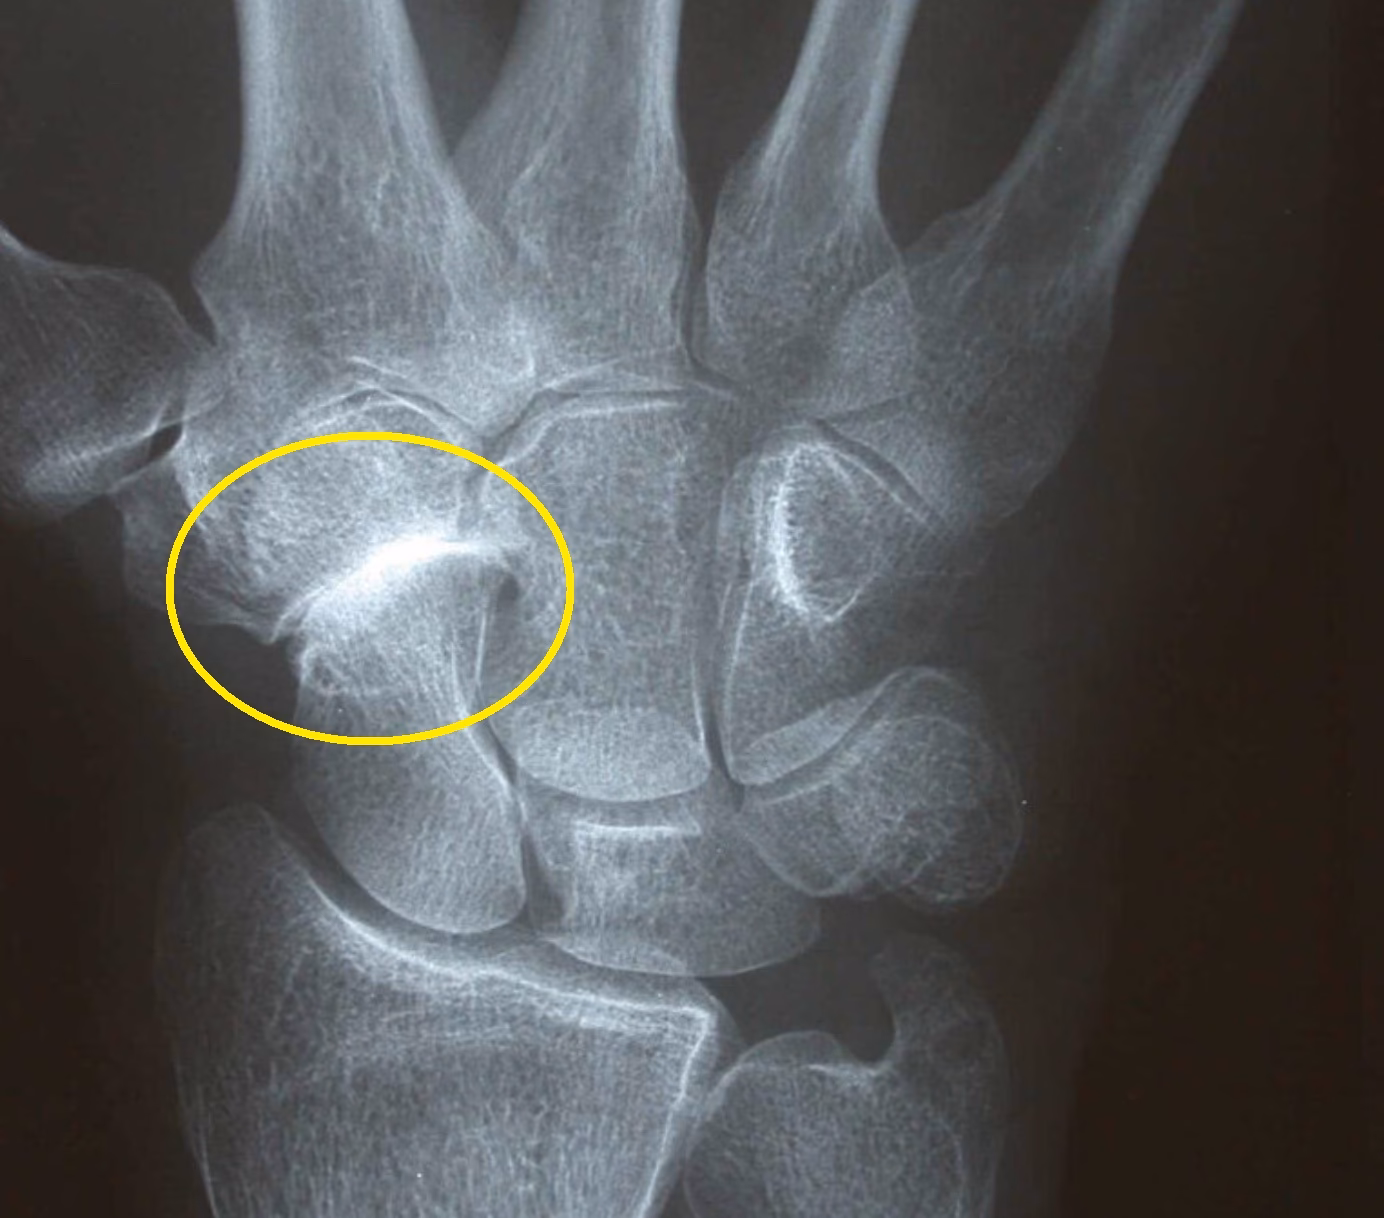

Diagnosen stilles typisk af en læge eller en speciallæge baseret på en kombination af patientens sygehistorie, en grundig klinisk undersøgelse af håndleddet og billeddiagnostik. Lægen vil mærke efter ømhed, vurdere bevægelighed og teste gribestyrken. Et almindeligt røntgenbillede er ofte tilstrækkeligt til at bekræfte diagnosen ved at vise afsmalnet ledspalte, knogleudvækster (osteofytter) og øget knogletæthed (sklerosering) omkring STT-leddet.